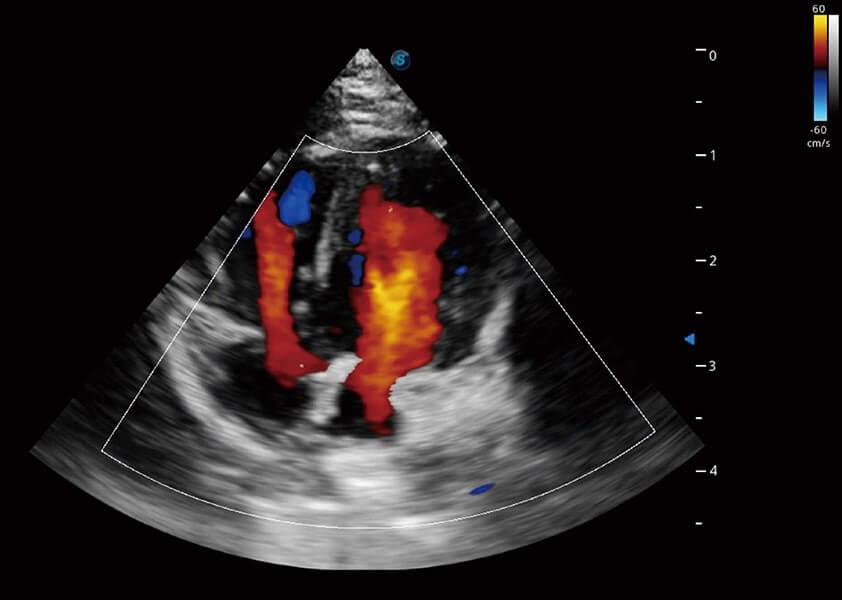

ProPet 60 作为一款高端台式动物超声设备,为动物医生的日常诊断提供了一系列贴合动物临床需求、解决临床实际问题的高级成像功能。凭借全系列高清探头,满足医生对腹部、心脏、生殖、浅表、肌骨等成像的所有需求,切实帮助您提升检查效率,提高诊断信心。

兽用彩色多普勒超声诊断系统

动物是人类最亲密的朋友和最值得信赖的伙伴。新葡的京集团8814检测站也一直致力于探索动物专用的超声影像解决方案。 全新推出的ProPet系列,是新葡的京集团8814检测站在动物超声影像智能化、专业化、精准化的一次跨越式革新。动物不能用言语来表述自己的不适,通过超声影像,ProPet系列搭建了动物医生与不同物种沟通的“桥梁”,为动物医生注入了“治愈之力”。